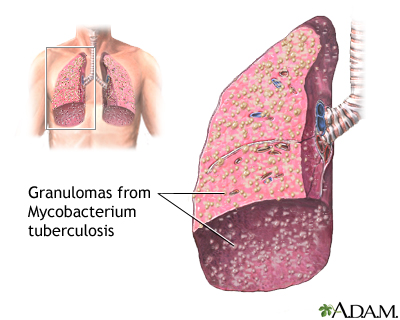

Pulmonary tuberculosis (TB) is a contagious bacterial infection that involves the lungs. It may spread to other organs.

Pulmonary TB is caused by the bacterium Mycobacterium tuberculosis (M tuberculosis). TB is contagious. This means the bacteria may spread from an infected person to someone else. You can get TB by breathing in air droplets from a cough or sneeze of an infected person. The resulting lung infection is called primary TB.

Most people recover from a primary TB infection without further evidence of the disease. The infection may stay inactive (dormant) for years. In some people, it becomes active again (reactivates).

Most people who develop symptoms of a TB infection first became infected in the past. In some cases, the disease becomes active within weeks after the primary infection.